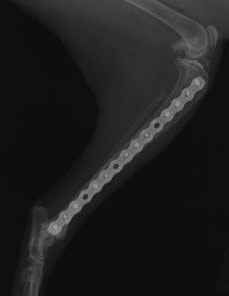

症例3:キルシュナーワイヤーのピンニングによる整復

ペルシャ猫 11ヶ月齢 雄

他院にて左大腿骨遠位の成長板骨折(salter-harrisⅠ型)が認められており、治療相談を目的として来院。当院にて、キルシュナーワイヤーを用いたピンニングにより骨折部位の整復を行いました。術後の経過は良好で、現在も経過観察中です。

術後レントゲン